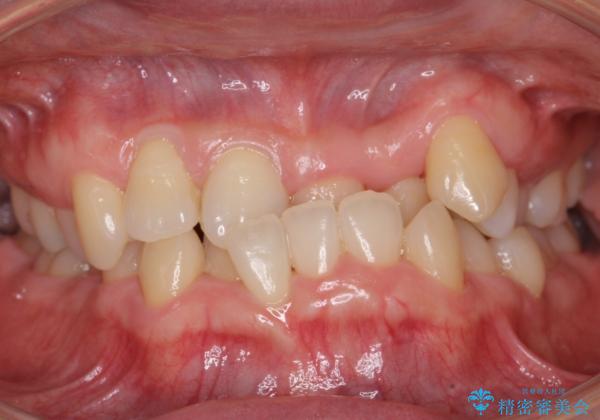

受け口 絶対に顎の手術はしたくない

- 受け口を主訴に来院。

下あごが大きく、顎の手術を含めた矯正をおすすめしましたが、手術は怖いので絶対にしたくないとのことでした。

歯並びのみを治す矯正は難しく、長期にわたる治療になるとご説明しました。

かみしめもあり、骨も固く、歯根も長いためなかなか歯が動かず、患者様も治療する側も忍耐を要する長期戦となりました。